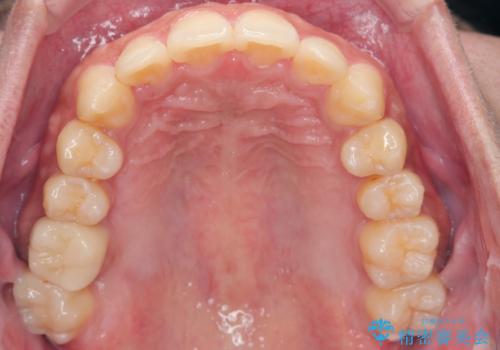

- 奥歯の噛み合わせは特に問題ないため臼歯を特に大きく動かす事はなく。

歯と歯の間を削る(ディスキング)、拡大を行いマウスピースで矯正を行いました。

がたつきもなくなりスッキリした歯並びになりました。